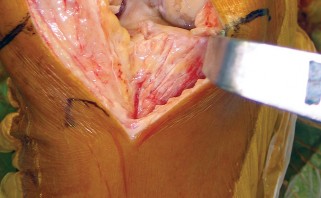

يركز هذا النهج على استخدام فتحة المفصل شبه الرضفية الإنسية المحدودة (Limited Medial Parapatellar Arthrotomy) وشق العضلة الرباعية المحدود، وهو جزء من مجموعة من الأساليب المعدلة التي توفر وصولاً ورؤية محدودين، ولكن يمكن تحويلها إلى نهج تقليدي إذا لزم الأمر. هذا يعني أن الجراح يمكنه البدء بتقنية أقل توغلاً، مع الاحتفاظ بالقدرة على التكيف إذا كانت الحالة تتطلب رؤية أوسع.

يُعد النهج شبه الرضفي الإنسي المحدود في جراحة استبدال مفصل الركبة الكلي بالحد الأدنى من التدخل الجراحي خيارًا مألوفًا ومتعدد الاستخدامات، وقد تطور مع إضافة أدوات أصغر وأكثر كفاءة. يتميز هذا النهج بقدرته على التكيف مع مجال العمليات المحدود في الركبة، مما يسمح بتشريح جراحي محدود دون المساس بالإجراء أو النتائج.

كيف يؤثر التدخل الجراحي المحدود على الأنسجة

في جراحة استبدال مفصل الركبة التقليدية، يتم إجراء شق كبير لتمكين الجراح من الوصول الكامل إلى المفصل ورؤية جميع الهياكل. هذا قد يتطلب قطعًا أوسع في العضلات والأوتار والأنسجة الرخوة المحيطة. في المقابل، يهدف النهج شبه الرضفي الإنسي المحدود إلى: